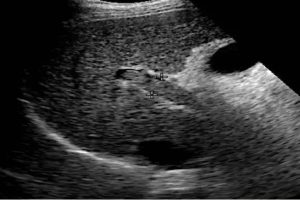

Diplomados en Ultrasonografía